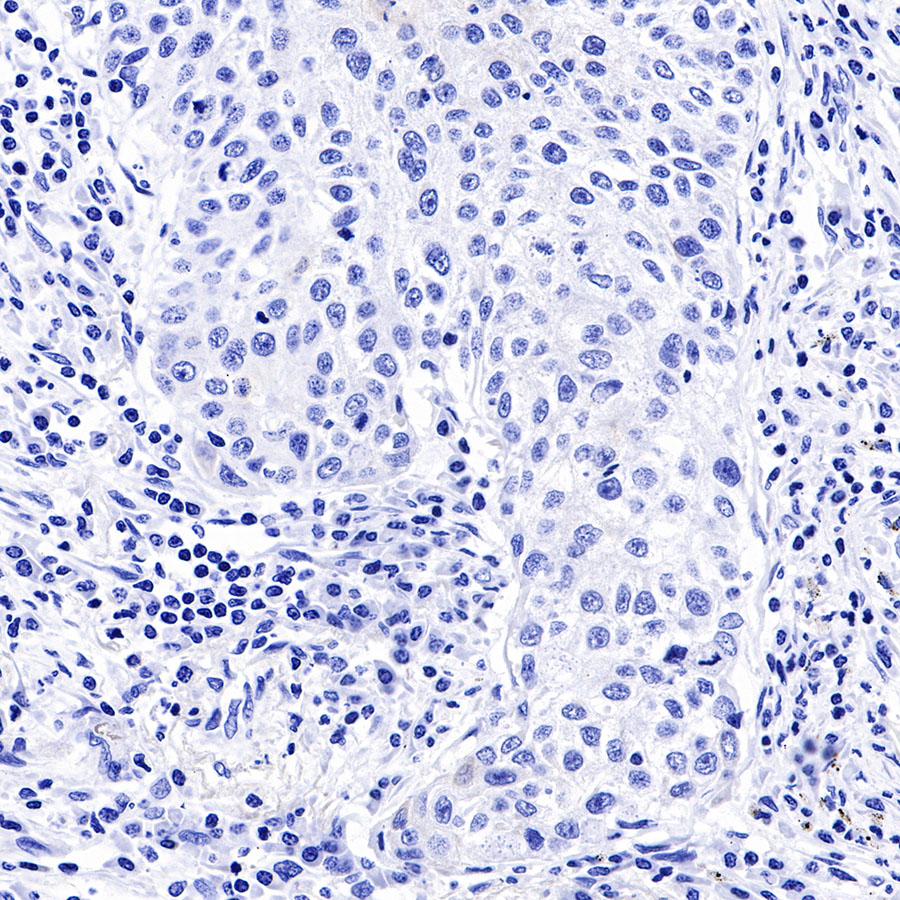

| IHC-P |

1:2000 |

Background

Cytokeratins are proteins of cytoskeletal intermediate filaments, and their main function is to enable cells to withstand mechanical stress. In humans, 20 different cytokeratin isotypes have been identified. Cytokeratins 8, 18, 19, and 20 have been associated with bladder. Cytokeratin 18 (KRT18, also called K18), found in epithelial cells, is released from hepatocytes upon death.